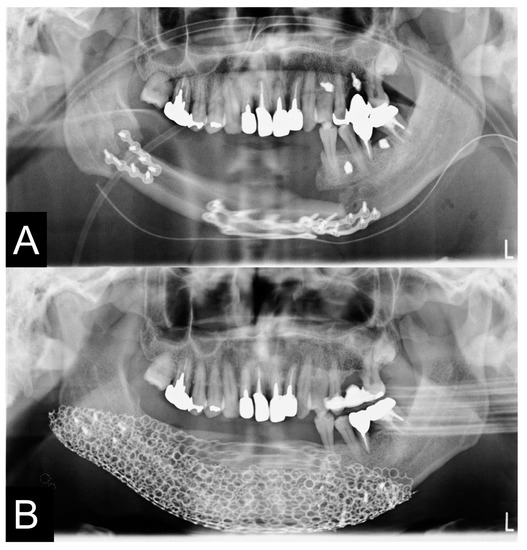

2.8. Clinical Procedures

3.3. Evaluation of Reconstructed Mandible

2.5. 3D Printing Model Fabrication and Titanium Mesh Pre-Bending